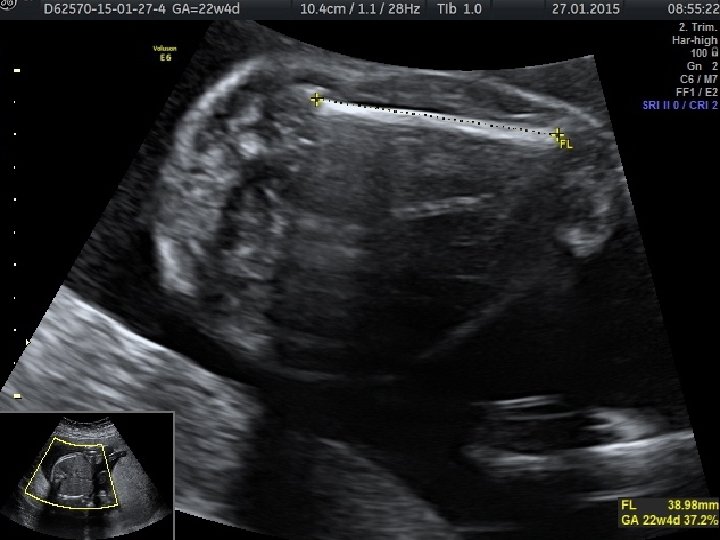

• Anormal biyometri saptanan hastalarda anormal fetal büyümenin fetal, plasental veya maternal nedenlerinin belirlenmesi amacıyla klinik ve ultrasonografik muayene yapılması gerekir. • Tahmini fetal ağırlığın saptanması için birçok formül önerilmiştir. • Bu formüllerin birçok parametre içermesine (biparietal çap, oksipitofrontal çap, baş çevresi, femur uzunluğu, abdominal çap ve abdominal çevre) karşın tahmini fetal ağırlıkta yanılma ortalama %10 -15 arasındadır ve bu oran %25’e kadar çıkabilmektedir.

• Gebelik yaşının tespitinde erken gebelikte en değerli ultrasonografik ölçüm parametresi CRL’dir. • İkinci trimesterda ise BPD ve HC daha doğru sonuçlar verir. • Üçüncü trimesterda ise en değerli ölçüm AC’dir. AC fetal büyüme ve ağırlık için en değerli parametredir.